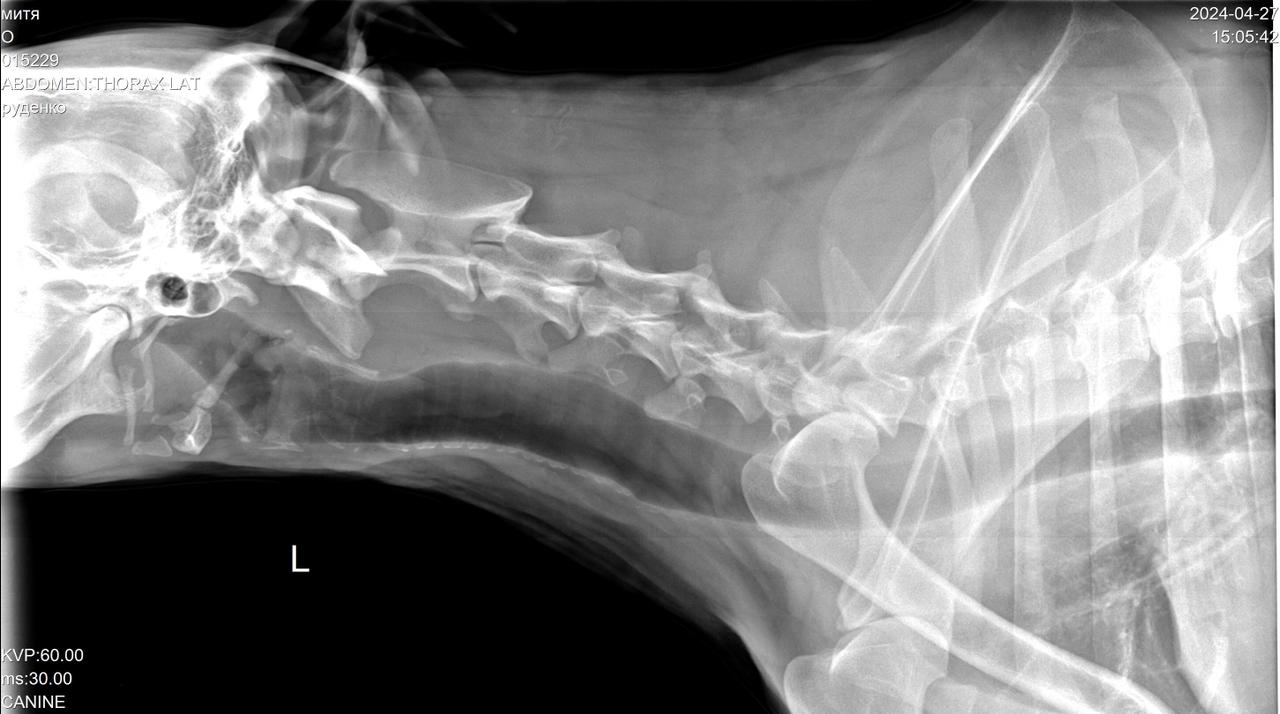

Сегодня Катюша возила Митю на рентген.

Вложения

IMG-20240427-WA0028.jpg

IMG-20240427-WA0029.jpg

IMG-20240427-WA0030.jpg

IMG-20240427-WA0031.jpg

IMG-20240427-WA0032.jpg